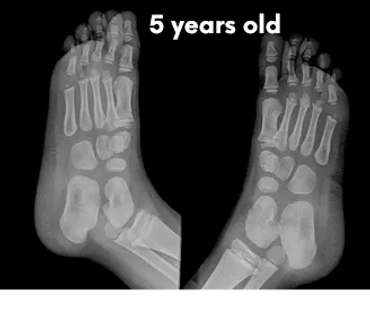

Babies’ feet are very soft and mostly made of cartilage in the first years of life. Their bones are still forming, and they have a thick layer of fat that makes their feet look chubby. This is why it’s important not to restrict their feet with tight or rigid shoes, as it could affect the natural shape and growth.

Let's check what their foot bones look like.

Pictures below will let you understand how babies' feet are developed.

Dear parents, children’s feet are developing structures, and the absence of an arch is a typical stage of development. The developing foot is not structurally ‘flat’; it is a highly compliant and plastic, that can respond to multiple factors, many of which we do not understand. Detailed X-RAY pictures above, let us understand that babies' foot bones are not connected till the teen years. Only at the age of 14, we may consider that the bones in the feet are developed and have reached their connections.

At the age of 18, we have fully completed foot structure, where muscles and bones create the whole support system.

Flat feet are a normal stage of development for children under the age of 3. The arch on the inside of the foot has not yet formed, and as children grow and walk, the soft tissues in the feet gradually tighten, shaping the arch over time. Most children have what is called a flexible flatfoot, where the arch only appears when they sit, tiptoe, or when the big toe is gently bent back.